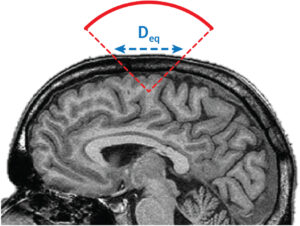

A new consensus paper co-authored by Jean-François Aubry and David Attali has been recently published in Brain Stimulation: “ITRUSST Consensus on Biophysical Safety for Transcranial Ultrasound Stimulation”

Oct 24, 2025

Toward global safety standards for transcranial ultrasound stimulation: new publication in Brain Stimulation